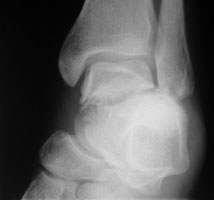

A | Lateral radiograph of the ankle. This shows a displaced fracture of the talar neck. |